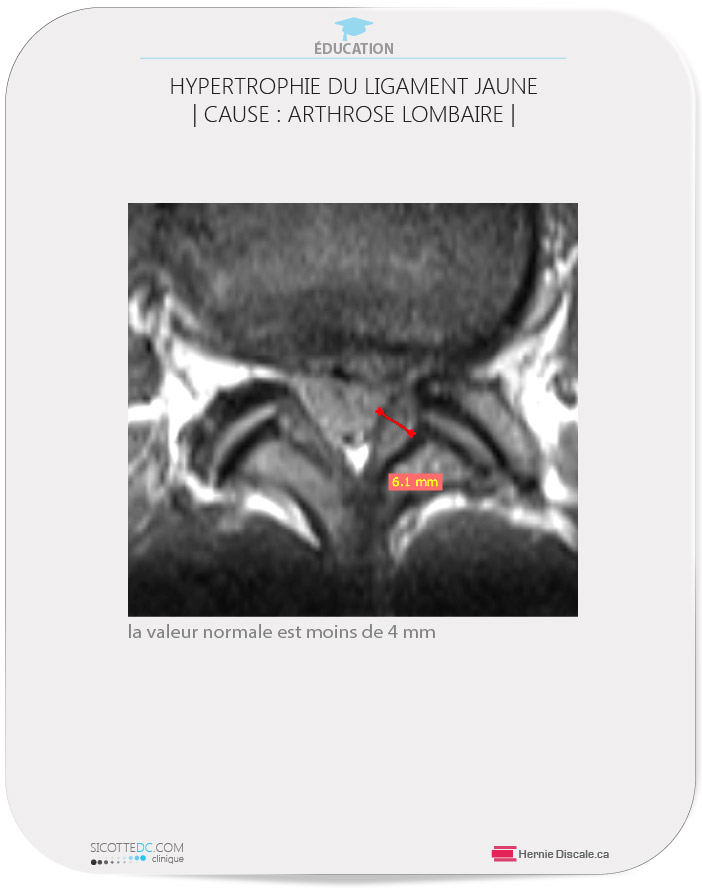

- contribue à l’épaississement du ligament jaune (*3),

HYPERTROPHIE DU LIGAMENT JAUNE | CAUSE DE L’ARTHROSE LOMBAIRE | (*3)